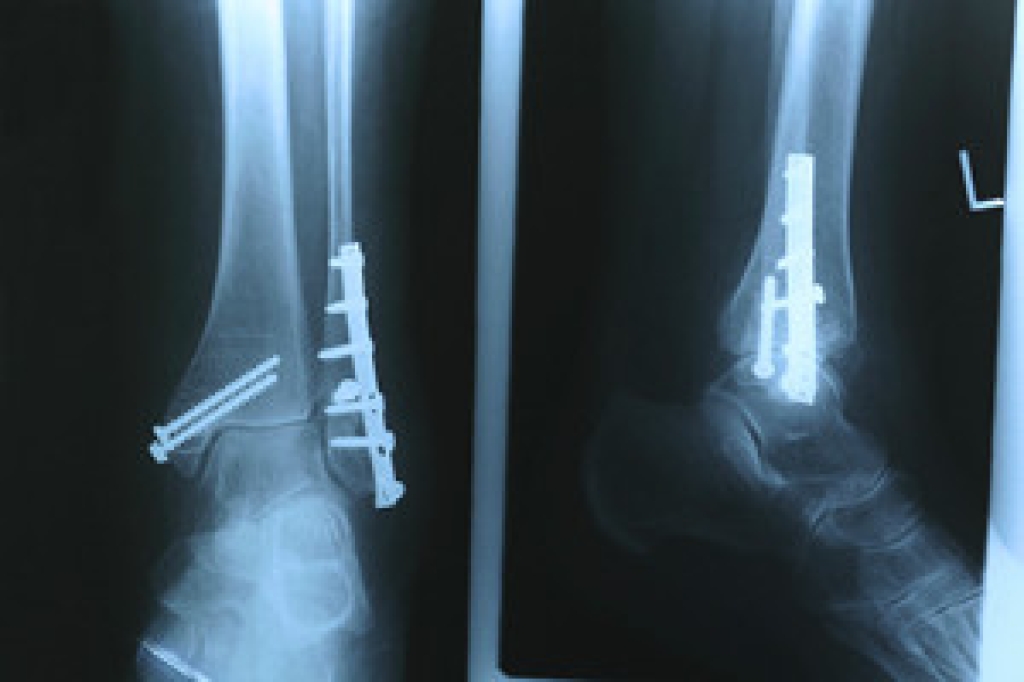

A broken ankle may require surgery if the ankle is unstable and the bone that is broken is displaced. During the procedure, the surgeon realigns the affected bones and fixes them in the proper position using a fixation device, such as a screw, steel pins, or stabilizing rods. Recovery from this surgery can take up to 12 weeks and requires wearing a cast or boot. While not everyone is a good candidate for surgery, leaving a fractured ankle untreated can lead to ankle arthritis and pain. If you have broken your ankle, please consult with a podiatrist to find the right treatment for you.

A broken ankle is experienced when a person fractures their tibia or fibula in the lower leg and ankle area. Both of these bones are attached at the bottom of the leg and combine to form what we know to be our ankle.

When a physician is referring to a break of the ankle, he or she is usually referring to a break in the area where the tibia and fibula are joined to create our ankle joint. Ankles are more prone to fractures because the ankle is an area that suffers a lot of pressure and stress. There are some obvious signs when a person experiences a fractured ankle, and the following symptoms may be present.